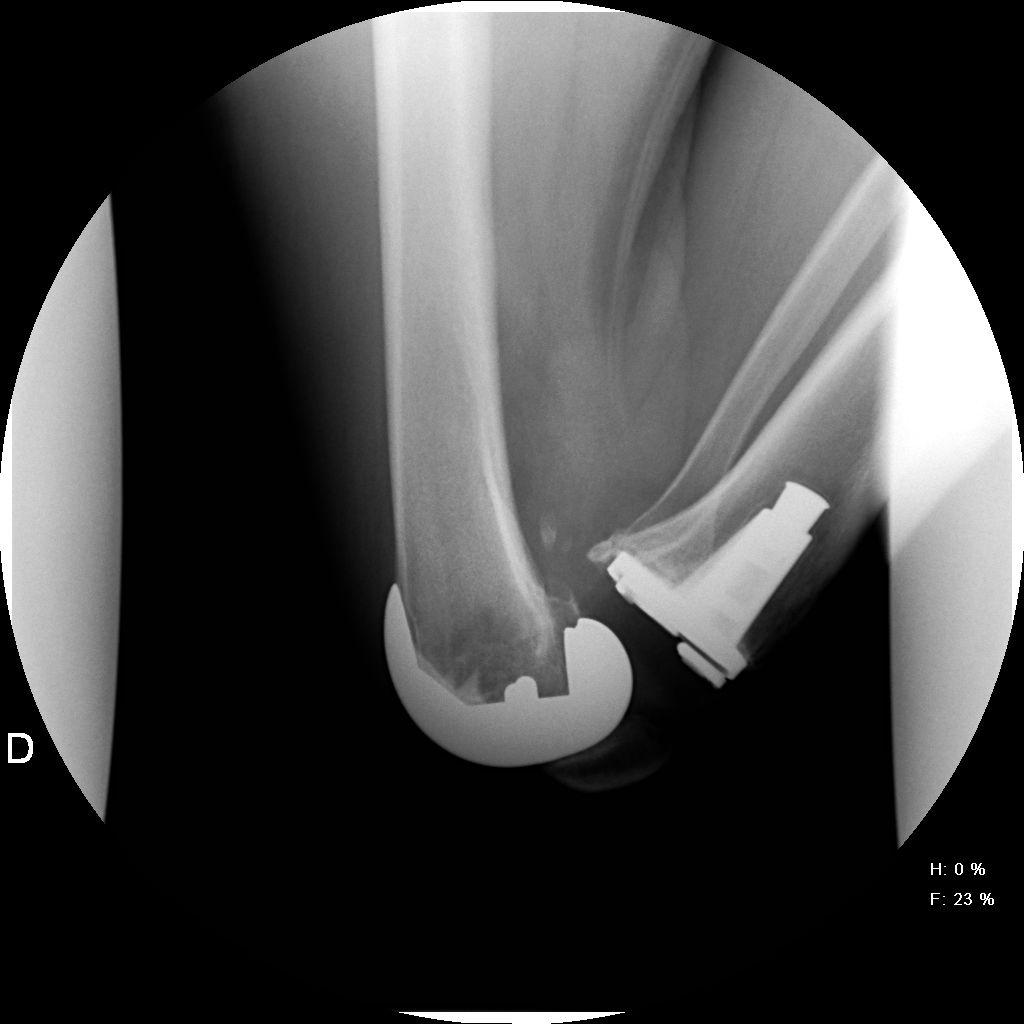

Introducción: El objetivo de este trabajo comparativo fue analizar los resultados funcionales y el rango de movimiento de rodilla entre dos grupos de pacientes con artroplastia total de rodilla: uno utilizando prótesis de alta flexión y el otro con un diseño convencional. Materiales y Métodos: Setenta y cuatro pacientes fueron operados con artroplastia total de rodilla con prótesis de Zimmer NexGen®, EE.UU. Veintidós (grupo A) fueron tratados con diseño de alta flexión. Dos con artritis reumatoide fueron excluidos. Cuarenta y dos pacientes fueron tratados con una convencional, 21 de ellos fueron excluidos, por lo que el grupo B estaba conformado por 21 pacientes. La evaluación funcional se realizó con el Knee Society Score (KSS), el Western Ontario and McMaster Universities osteoathritis index y la escala analógica visual.Resultados: El promedio de flexión máxima preoperatoria fue de 99º en el grupo A y de 106º en el grupo B. En el posoperatorio, el promedio de flexión máxima del grupo A subió a 114º, con un aumento promedio de 15º y, en el grupo B, a 118º con una ganancia promedio de 12º. No hubo diferencias estadísticamente significativas (p <0,05). El puntaje KSS preoperatorio del grupo A fue de 36/48 y mejoró a 90/92. En el grupo B, fue de 46/49 y de 94/90 en el posoperatorio.Conclusión: Las evaluaciones clínicas funcionales y radiológicas son favorables en los dos diseños de prótesis evaluados. Este estudio muestra que no hay diferencias significativas entre el rango de movimiento de una prótesis de alta flexión y una prótesis convencional luego de un año de seguimiento.Descargas